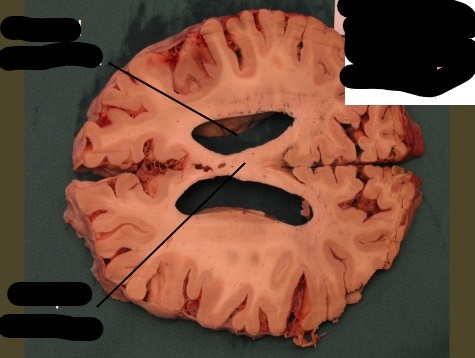

label, note important features

only portion of corona radiata seen right now are association fibers (which interconnect ipsilateral gyri) there are no internal capsule or lateral ventricles seen, indicating this cut is very rostral (pre-frontal cortex)